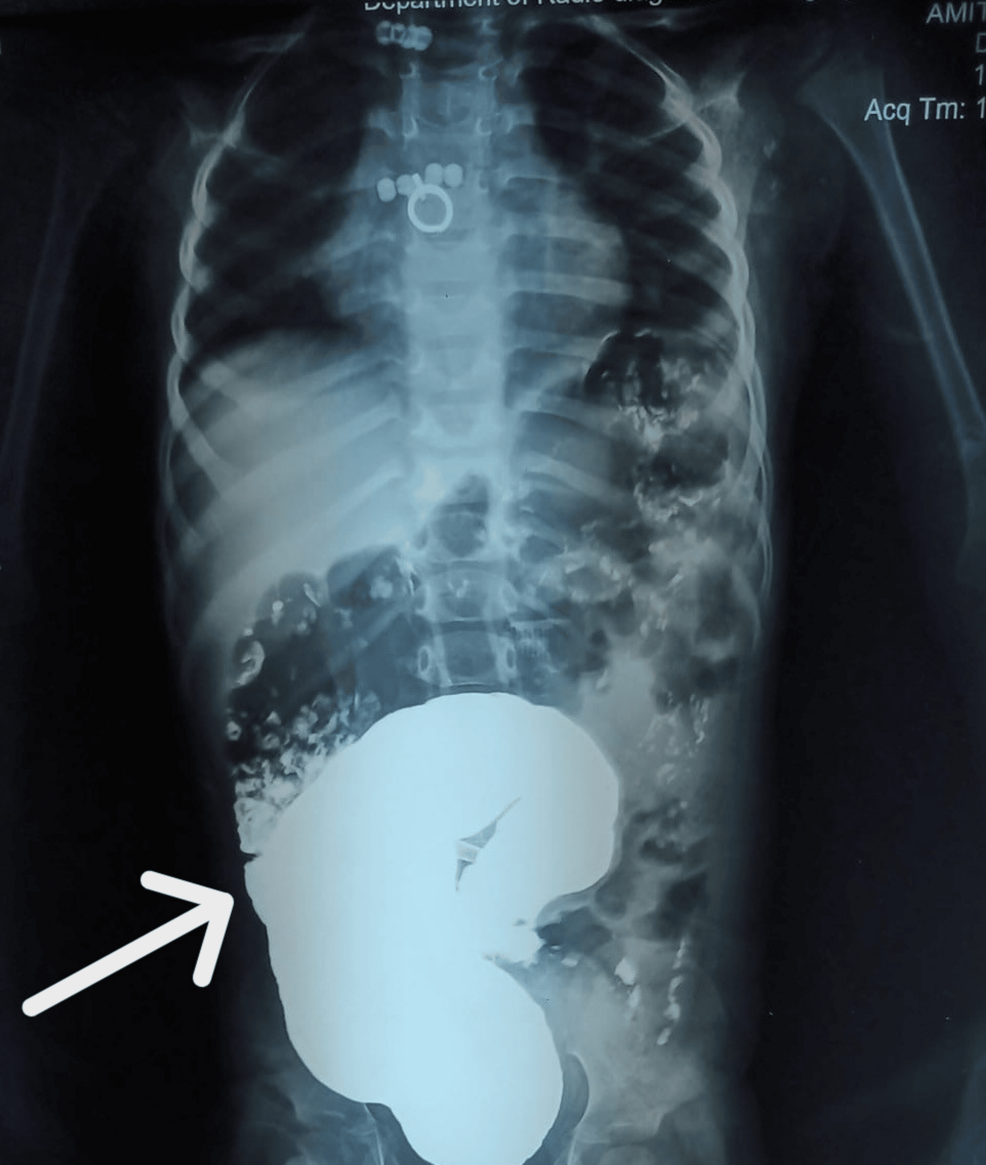

Una rara condición, la ectasia miduréterica con estenosis, puede presentarse en bebés como una obstrucción intestinal, imitando la enfermedad de Hirschsprung. Un reciente caso publicado en Cureus detalla la experiencia de un lactante de tres meses que inicialmente fue evaluado por una posible enfermedad de Hirschsprung debido a una obstrucción intestinal y una masa abdominal en el lado izquierdo.

Durante la exploración quirúrgica, se descubrió que la obstrucción no era causada por problemas en el intestino grueso, sino por una dilatación quística en la parte media del uréter, que comprimía el colon. Las porciones proximal y distal del uréter se encontraron normales.